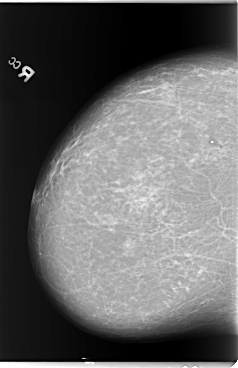

B_3105_1.LEFT_MLO

LEFT_MLO LINES 5840 PIXELS_PER_LINE 4136 BITS_PER_PIXEL 12 RESOLUTION 50 OVERLAY

FILE: B_3105_1.LEFT_MLO.OVERLAY

TOTAL_ABNORMALITIES 1

ABNORMALITY 1

LESION_TYPE CALCIFICATION TYPE AMORPHOUS DISTRIBUTION CLUSTERED

LESION_TYPE MASS SHAPE OVAL MARGINS ILL_DEFINED

ASSESSMENT 4

SUBTLETY 2

PATHOLOGY BENIGN

TOTAL_OUTLINES 1

BOUNDARY